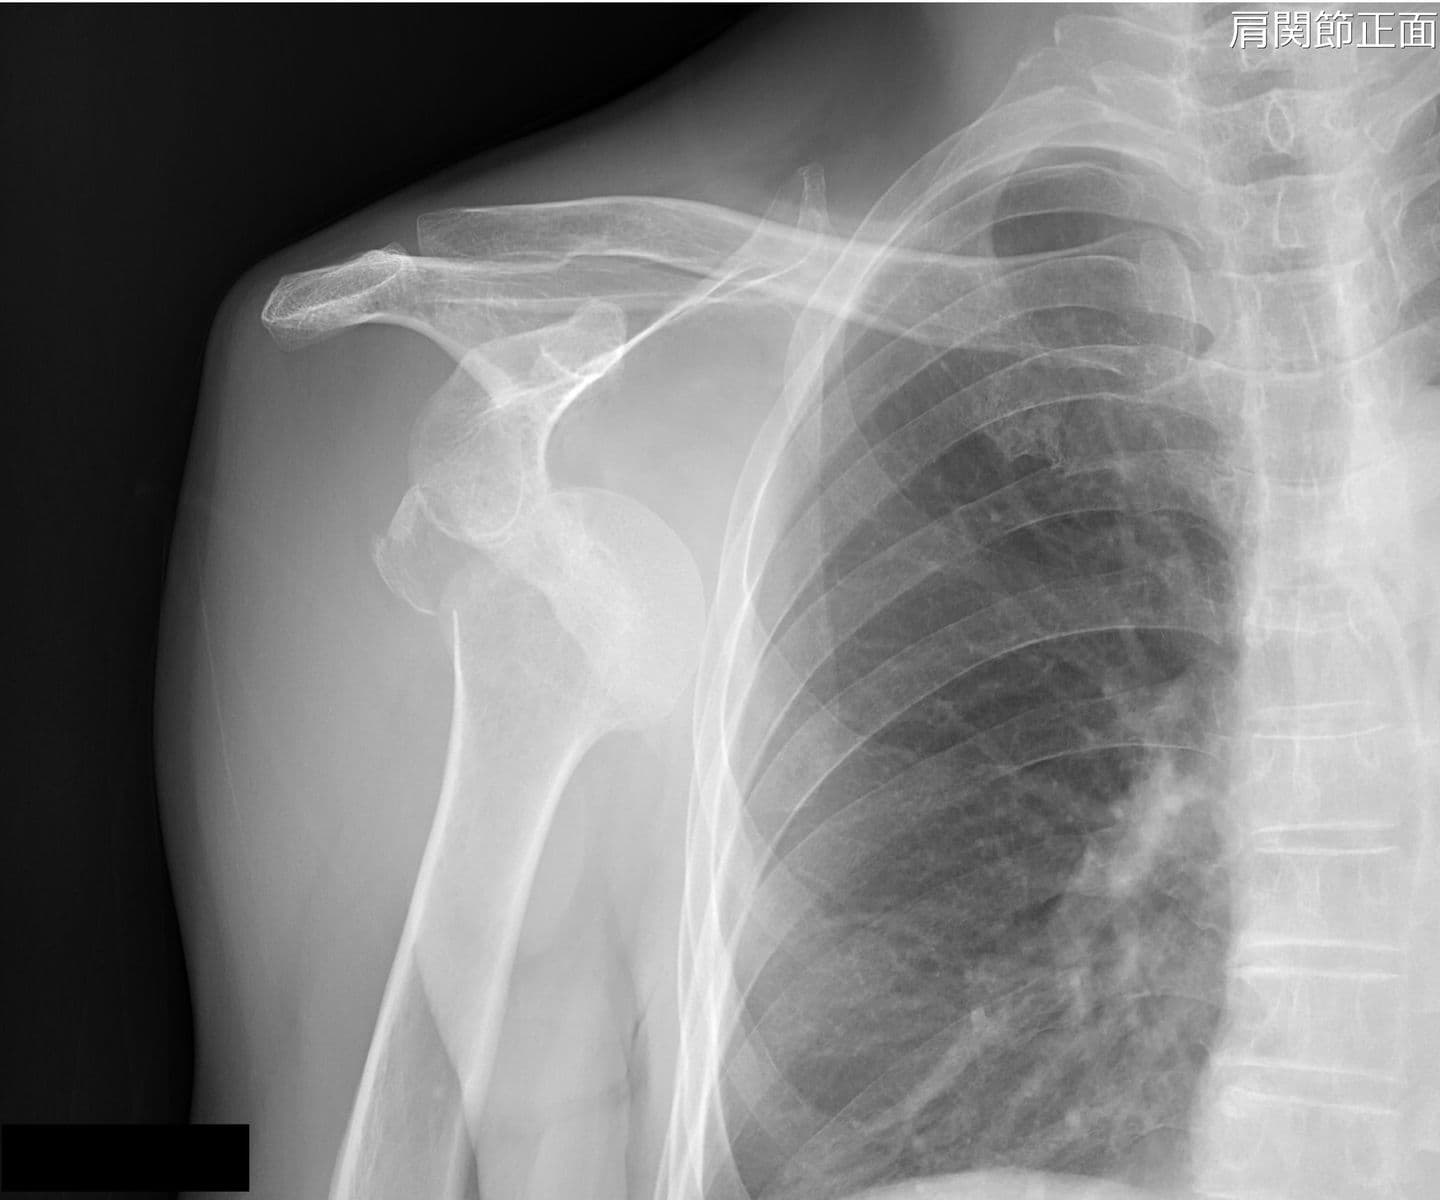

整形外科では、椎間板ヘルニアなどによる神経障害の痛みを軽減させる神経根ブロックなどの治療を行っています。また、脊髄腔や様々な関節腔(肩関節、股関節、手関節など)に造影剤を注入し、関節腔の形態を調べます。

寝台が広いため、骨折や関節脱臼をX線透視下で確認しながらの整復を行っています。